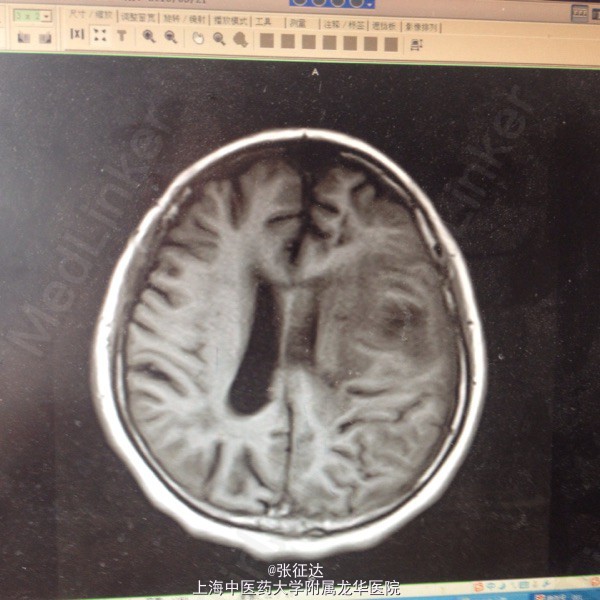

神情,GCS14分,右侧肢体肌力III级,病理症(-)。头颅CT:左侧顶叶区占位

复查头颅MR表现为左侧顶叶占位。择期全麻下行手术治疗后取病理,提示脑脓肿